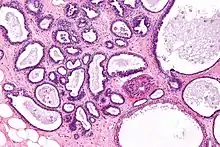

![]() | Vesicular mole | Micrograph of vesicular mole showing oedematous chorionic villus with circumferential proliferation of trophoblasts. | Category: Histopathology of chorionic villi | chorionic villi |